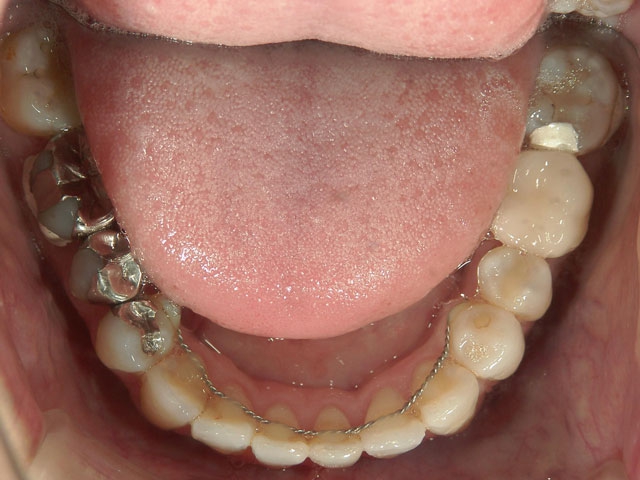

矯正歯科 治療前 外科手術併用(コルチコトミー)、非抜歯

矯正_灰色.pngno.7_6967_治療前_下_01.jpg矯正_灰色.png